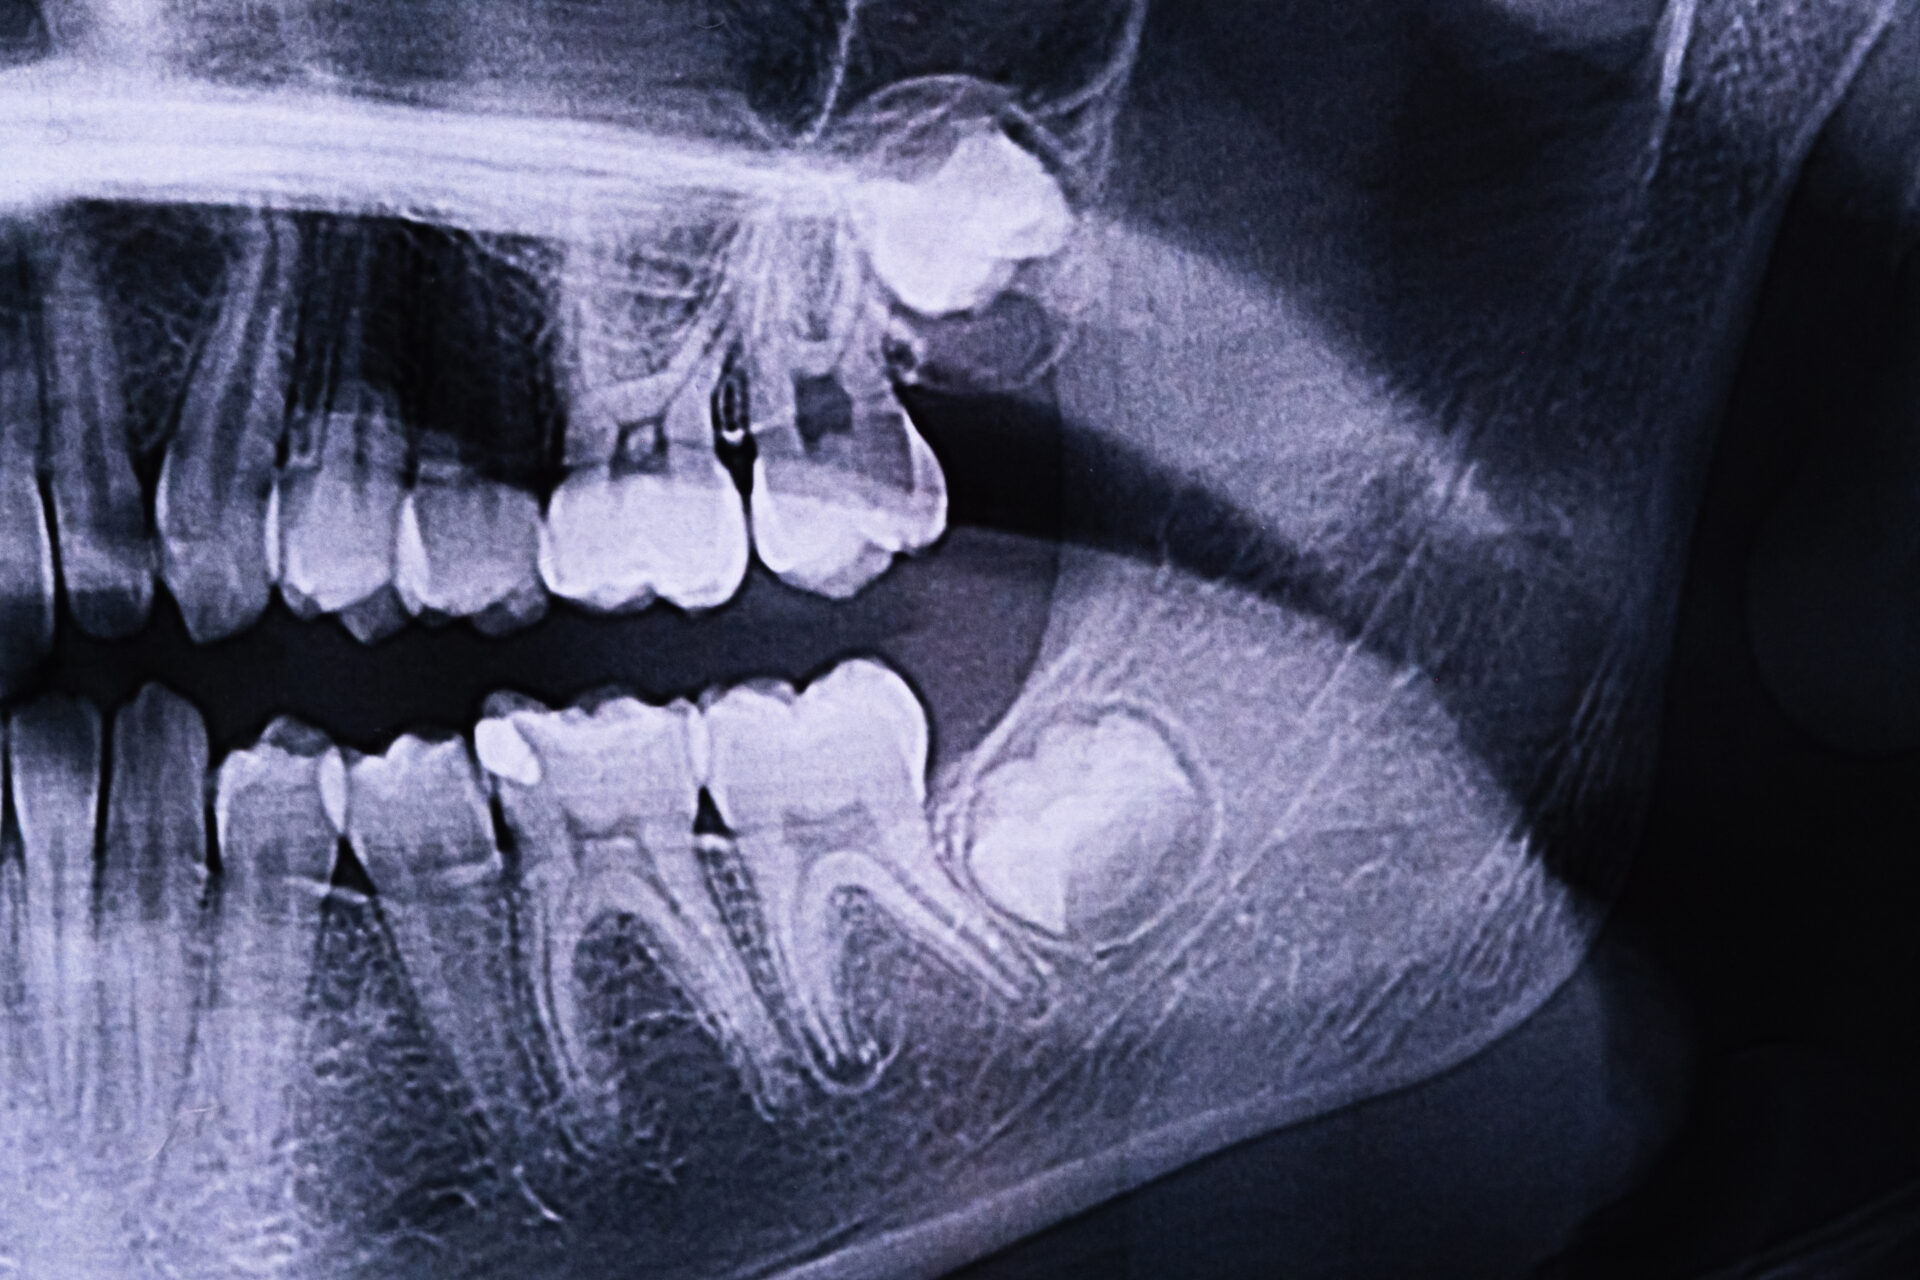

Wisdom teeth are a valuable asset to the mouth when they are healthy and properly positioned. Often, however, they cause problems and require removal. When the jaw isn’t large enough to accommodate wisdom teeth, they can become impacted. Impacted wisdom teeth may grow sideways, emerge only part way through the gum or remain trapped beneath the gum and bone.

Wisdom teeth don’t always cause symptoms, but common warning signs include: pain or swelling at the back of the mouth, red, swollen, or bleeding gums around the molars, jaw stiffness or difficulty opening the mouth, headaches or earaches, bad breath or an unpleasant taste, crowding or shifting of other teeth, and recurring infections near the molar area. If you notice any of these symptoms, book a consultation at Toorak Village Dental Care. Our dentists will examine your wisdom teeth with the help of digital X-rays and determine the best course of action.

Our Toorak dentist starts with a detailed examination and X-rays to evaluate the position and development of your wisdom teeth. This helps us decide whether extraction is needed and how to approach it.